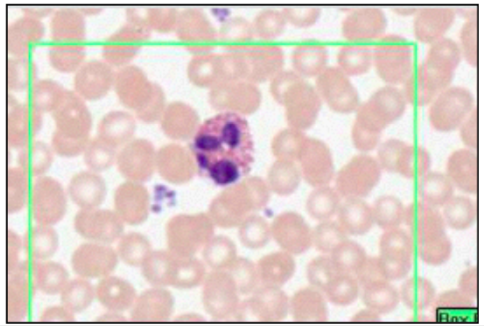

NEUTROPHILS - POLYMORPHONUCLEAR LEUKOCYTES (LEISHMAN’S STAIN)

- multi-lobar nucleus

- most numerous

- phagocytic

- engulf and destroy bacteria

- leave blood stream to enter tissue @ infection site

fine granules = GRANULOCYTES

- primary - lysosomes, acid hydrolases, antibac and digest

- secondary - neutrophil specific, regulation of inflammation response

- tertiary - facilitate insertion of proteis to cell membrane

lobes = 2-4, number increases with age